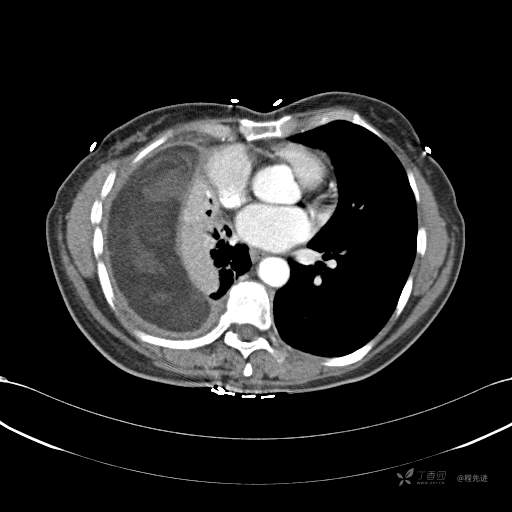

患者性别:女

患者年龄:51岁

简要病史:胸闷半年